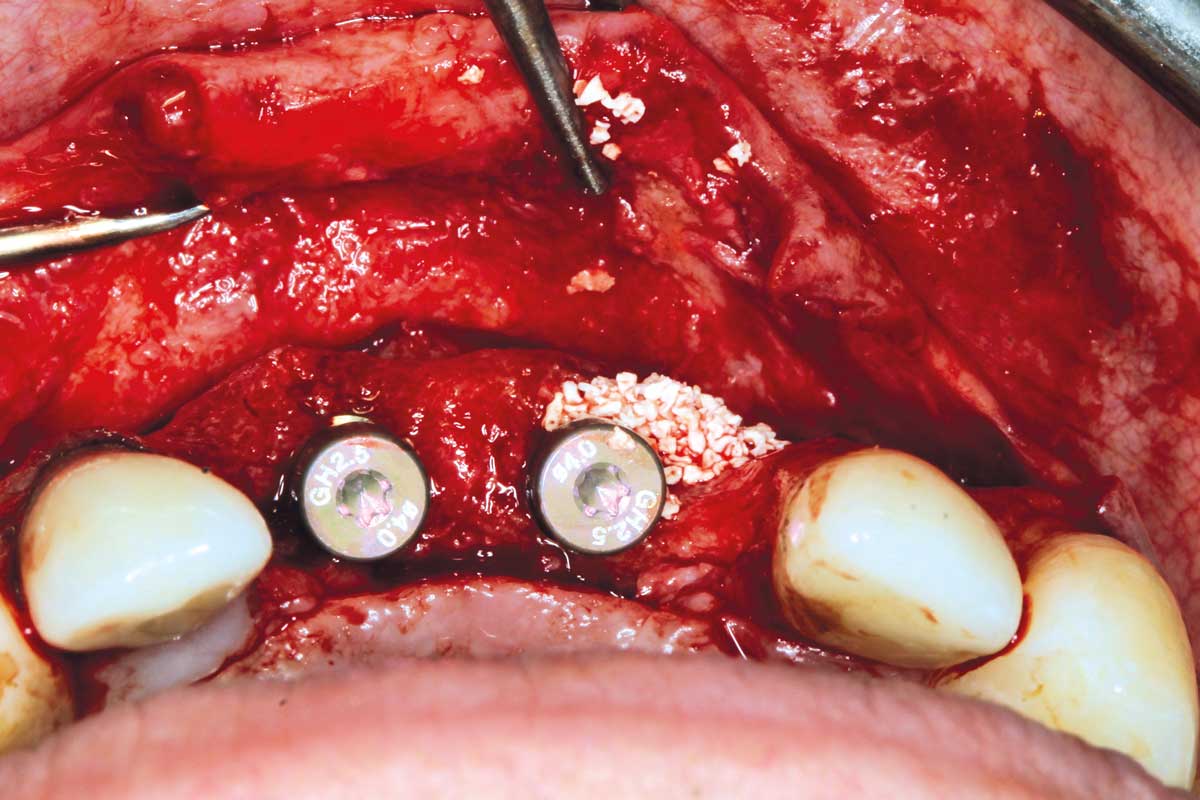

17/26 - Insertion of two Straumann BLX implants 3.75 x 14 mm / 3.75 x 12 mm

Ridge augmentation in the maxilla with maxgraft® bonebuilder in the aesthetic zone - Dr. M. Kristensen

19/26 - Contouring with cerabone®